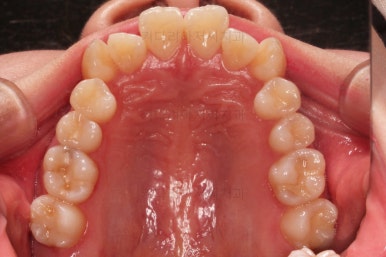

마찬가지로 초진 시 입안의 모습인데요.

전반적으로 약간 삐뚤지만 특히 윗니 앞니가 삐뚤고요.

송곳니는 덧니처럼 튀어나와 보이네요.

그리고 전반적으로 치아가 앞쪽으로 경사되어 있어서 앞니는 뻗친 느낌이 있네요.

가지런하게 하면서 앞니를 뒤로 당겨줘야 여러 가지 문제점들이 개선되기 때문에 발치교정을 했어요.